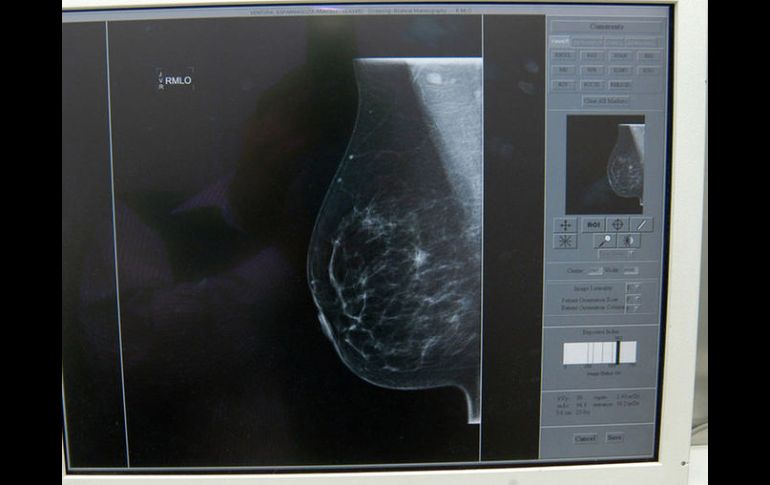

Jalisco | Aumentan muertes por cáncer de mama 'El cáncer lo sacude a uno' La autoridad estatal no prevé reducir los casos de cáncer de mama. La meta, ante las complicaciones, es mantener la incidencia Por: EL INFORMADOR 14 de octubre de 2014 - 03:10 hs Jalisco es el quinto lugar nacional por número de muertes por cáncer de mama en 2014. NTX / ARCHIVO GUADALAJARA, JALISCO (14/OCT/2014).- La primera biopsia de Rosa María Equihua Serrano salió negativa. Pero la cicatriz de esa primera intervención le siguió doliendo y cuando acudió a que le hicieran otra detectaron el tumor que convirtió lo que sería una cirugía ambulatoria en una mayor. Luego de quitarle el tumor –lo que implicó que también perdiera su seno– le dieron seis sesiones de quimioterapia como prevención, luego, cinco años de tratamiento con pastillas. Sin embargo, un año y medio después, en enero pasado, se comenzó a sentir mal, con tos. No podía respirar. Fue al Seguro Social, en donde le ordenaron radiografías y estudios, pero la tardanza de la cita para ello la llevó a un hospital privado del que no salió hasta que le hicieron una punción, pues uno de sus pulmones estaba lleno de agua: el cáncer había vuelto. Así, en febrero le pusieron su primera quimioterapia de urgencia en el IMSS, y hasta ahorita está en tratamiento. Cada 22 o 28 días la repetía y así el tumor no avanzó, pero para comenzar a minarlo le cambiaron el medicamento, con el que lleva ya dos “quimios”. A Rebeca Gloria, el cáncer la encontró cuando tenía 65 años. Gracias a que todos los años se hacía una revisión fue posible actuar de manera oportuna cuando una biopsia reportó que había tejido maligno. Debido a que el tumor no estaba encapsulado, se le tuvo que retirar toda la mama. Tuvo tres meses de recuperación, seis meses de quimioterapia y 25 sesiones de radioterapia. Ahora la revisan checan cada seis meses. “Esta enfermedad lo sacude a uno porque, en mi caso, me hizo valorar muchas cosa, sobre todo, la vida. Veo que ya tengo que ver por mí y, aunque me haya dado a esta edad, valoro mucho la vida”, cuenta. Por ello, ahora es voluntaria en Grupo Reto y su experiencia es su mejor argumento. “Conozco mujeres que dicen que no se van a revisar, o fueron hace dos, tres o cinco años. Yo les diría que no hagan desidia, y que quienes ya lo tienen que reciban la enfermedad sin temor, sin miedo”. FRASE"Hemos estado luchando fuertemente para abatir y detectar tempranamente esta enfermedad, dado que la importancia de la detección precoz es mejor para la supervivencia "Jaime Agustín González Álvarez, secretario de Salud en Jalisco. GRUPO RETO A.CAsumen el reto de apoyar Desde hace 24 años, un grupo de mujeres que sobrevivieron al cáncer de mama se han propuesto ayudar a quienes se enfrentan a esa experiencia. Actualmente, entre cinco y siete voluntarias mantienen la misión de Grupo Reto A.C.: promover la detección oportuna del cáncer y prestar apoyo a quienes pasan por este trance. Así organizan una reunión semanal para apoyar a las mujeres que ya están operadas. Se les da información, libros, información sobre la radio y quimioterapia y, sobre todo, acompañamiento. Semestralmente atienden entre 200 y 300 mujeres, estima María del Refugio, presidenta de esta asociación civil desde 2004. Para lograr fondos se organizan algunas rifas, así como un desayuno mensual con cuyos ingresos se pagan los servicios básicos. La misma María del Refugio Palacios tiene 16 años operada de cáncer de mama. Su proceso fue devastador porque cuando recibió su diagnóstico, su suegra acababa de morir de cáncer de mama y ella la había atendido. Pensó que le pasaría lo mismo. La familia se unió en el mismo miedo, lo que resultó en lo que ahora define como una sobreprotección. Hoy, eso es parte del pasado. Lo que está en el presente es mantener su lucha por promover la información. Si pretende apoyar a este grupo puede hacer donativos al número de cuenta Santander 65-50460778-8. También se puede ayudar con apoyo en especie, como telas, pelucas, turbantes o mangas de compresión marca Yuzo. CAMPAÑAOctubre: mes de la sensibilización El “mes de sensibilización sobre el cáncer de mama” se celebra en todo el mundo en octubre. Contribuye en aumentar la atención y el apoyo prestados a la sensibilización, la detección precoz, el tratamiento y los cuidados paliativos. Los conocimientos actuales sobre las causas del cáncer de mama son insuficientes, por lo que la detección precoz sigue siendo la piedra angular de la lucha contra esta enfermedad. Cuando se detecta precozmente, se establece un diagnóstico adecuado y se dispone de tratamiento, las posibilidades de curación son elevadas. En cambio, cuando se detecta tardíamente, es raro que se pueda ofrecer un tratamiento curativo. En tales casos son necesarios cuidados paliativos para mitigar el sufrimiento del paciente y sus familiares. Prevención¿Cuáles son las causas? Las causas exactas, como otros cánceres, no se conocen. Sin embargo, se sabe que ciertos factores aumentan el riesgo: Antecedentes previos: las mujeres que ya presentaron un cáncer de mama con anterioridad, tienen el riesgo de presentar otro igual. Antecedentes familiares: las mujeres que tienen una pariente cercana, principalmente la madre o una hermana, corren también el riesgo de desarrollarlo. Antecedentes reproductivos: las mujeres mayores que nunca quedaron embarazadas, las que tuvieron su primer hijo después de los 30 años de edad y las que presentaron menopausia tardía. Otros factores: obesidad, tabaquismo e ingesta de hormonales. Nota: Estos factores aumentan el riesgo de padecer esta enfermedad. Prevén que siga en aumento La meta del Gobierno de Jalisco para este año no es reducir la tasa de mortalidad por cáncer de mama –de 12.73 defunciones por cada 100 mil mujeres– sino mantenerla, según la página del Monitoreo de Indicadores del Desarrollo de Jalisco. Al ser una enfermedad que ataca sobre todo a las mujeres mayores de edad, conforme los habitantes del país vayan envejeciendo es más probable que se registren más casos. Por ello es urgente potenciar la cultura de prevención temprana, señala Martha Arias Novoa, coordinadora estatal del Programa Cáncer de la Mujer de la Secretaría de Salud. Aunque hay casos de mujeres menores de 30 años que enfrentan esta enfermedad, principalmente ataca a las mayores de 40 años. Por eso es previsible que aumenten los casos en el futuro. Además del incremento en el número de mujeres en las edades de mayor riesgo, hay otros factores que pueden incrementar la posibilidad de contraer la enfermedad, como el desarrollo de la obesidad, el sedentarismo, la diabetes y la hipertensión. A estos factores hay que sumar el consumo de alcohol, el tratamiento prolongado de hormonas ante la menopausia y el factor hereditario –que no es el principal–, agrega Adrián Daneri Navarro, coordinador de Investigación del Centro Universitario de Ciencias de la Salud de la Universidad de Guadalajara. De esta manera, al igual que en otros países de ingresos medios y bajos, en México seguirá aumentando la incidencia –el número de casos nuevos– mientras no se trabaje en la identificación temprana. Por ello, desde que empieza a desarrollarse, se debe enseñar a las mujeres técnicas de autoexploración para saber cuándo una mama no es normal. Además, aunque en Jalisco el año pasado se realizaron cerca de 52 mil mastografías y éste se planea cerca de 80 mil –de las cuales ya van cerca de 51 mil–, este estudio se recomienda para mujeres mayores de 40 años. Para las menores de esa edad, este estudio no es tan efectivo, por lo que, en caso de sospecha, pueden platicar con su médico sobre la factibilidad de hacer un ecosonograma o incluso, una resonancia magnética, explica Daneri Navarro. Más investigación y capacitación También hay que aumentar el entrenamiento de los radiólogos para que puedan discriminar bien entre lo que sí es sospechoso o que apunta a que es cáncer de mama, y lo mismo puede decirse de los médico de primer y segundo nivel. Pero sobre todo es necesaria más investigación porque, ¿cómo puede uno prevenir si no se conoce qué es lo que causó el cáncer de mama?, cuestiona Daneri Navarro. Este 15 de octubre, el Centro Universitario de Ciencias de la Salud organizará un simposio en el que se hablará de la epidemiología, los factores de riesgo, la detección mediante la imagenología, el diagnóstico, el tratamiento y el pronóstico de la enfermedad. CLAVESLa lucha contra la enfermedad Quinto Jalisco ocupa ese lugar por número de muertes de cáncer de mama, con 455 fallecimientos en 2014. Día El 19 de octubre se conmemora el Día de la lucha contra el cáncer de mama, y el sector salud en Jalisco se unió para realizar la campaña preventiva “Pinta de rosa tu vida, con una detección oportuna”. Objetivo Que cada vez se encuentren casos en etapas tempranas de la enfermedad, y no en estudios tardíos, cuando los riesgos de muerte aumentan. Mamografías Del 14 al 30 de octubre, las instalaciones del Sistema DIF en Jalisco contarán con la presencia de un mastógrafo para realizar estudios gratuitos. Participantes Todo el sector salud tendrá 23 mastógrafos que circularán en todo Jalisco a mujeres de 40 a 69 años, y las menores de 40 serán objeto de una exploración mamaria y encuestas de factores de riesgo. Citas Para acudir al DIF Jalisco y acceder a una mamografía gratuita, se hacen en el teléfono 30309633. Ahí se dará toda la información sobre horarios y direcciones. Contacto Para mayor información, hablar a la Secretaría de Salud Jalisco, al 30305000. Sigue: #debateinformador¿Por qué motivos considera que la población no se realiza estudios preventivos para detectar enfermedades?Participa en Twitter en el debate del día @informador Temas Salud Mujeres Cáncer de mama Lee También ¿Cuáles son los beneficios de tomar jugo de betabel y cómo se prepara? Aprende a eliminar correctamente las bacterias de la esponja de la cocina Revive con la flor de muertos: beneficios del té de cempasúchil Cómo podrían los antibióticos incrementar el riesgo de cáncer colorrectal Recibe las últimas noticias en tu e-mail Todo lo que necesitas saber para comenzar tu día Registrarse implica aceptar los Términos y Condiciones